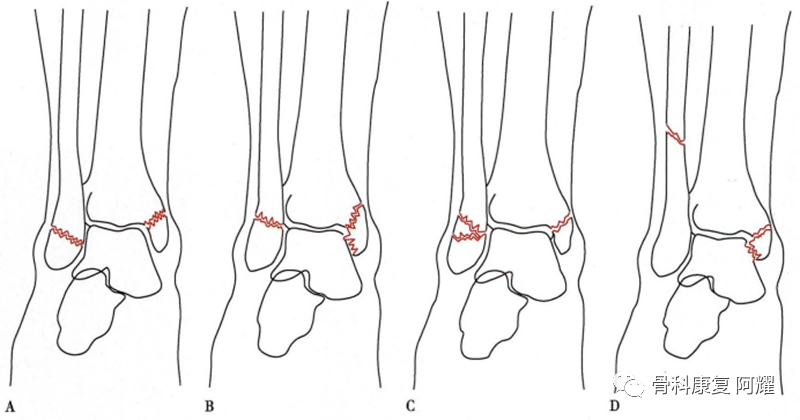

1.Lauge-Hansen 分型

Lauge-Hansen分型是通过实验模拟踝关节损伤机制建立的分型,是通过足在受伤时的位置和外力作用的方向产生的各种骨折类型。这种分型并不能完全包含所有的踝关节骨折,但是在临床上对于更好地理解损伤机制具有重要的意义。分型由两个词组成,共有4型,前一个词指受伤时踝关节的位置,后一个词指暴力的方向。最常见的骨折类型为旋后-外旋型(supination-external rotation, SER)占60%,之后是旋后-内收型占20%,其他为旋前型骨折(旋前-外展型和旋前-外旋型)。

踝关节骨折Lauge-Hansen分型

A旋后-内收型;B旋后-外旋型;C旋前-外展型;D旋前-外旋型